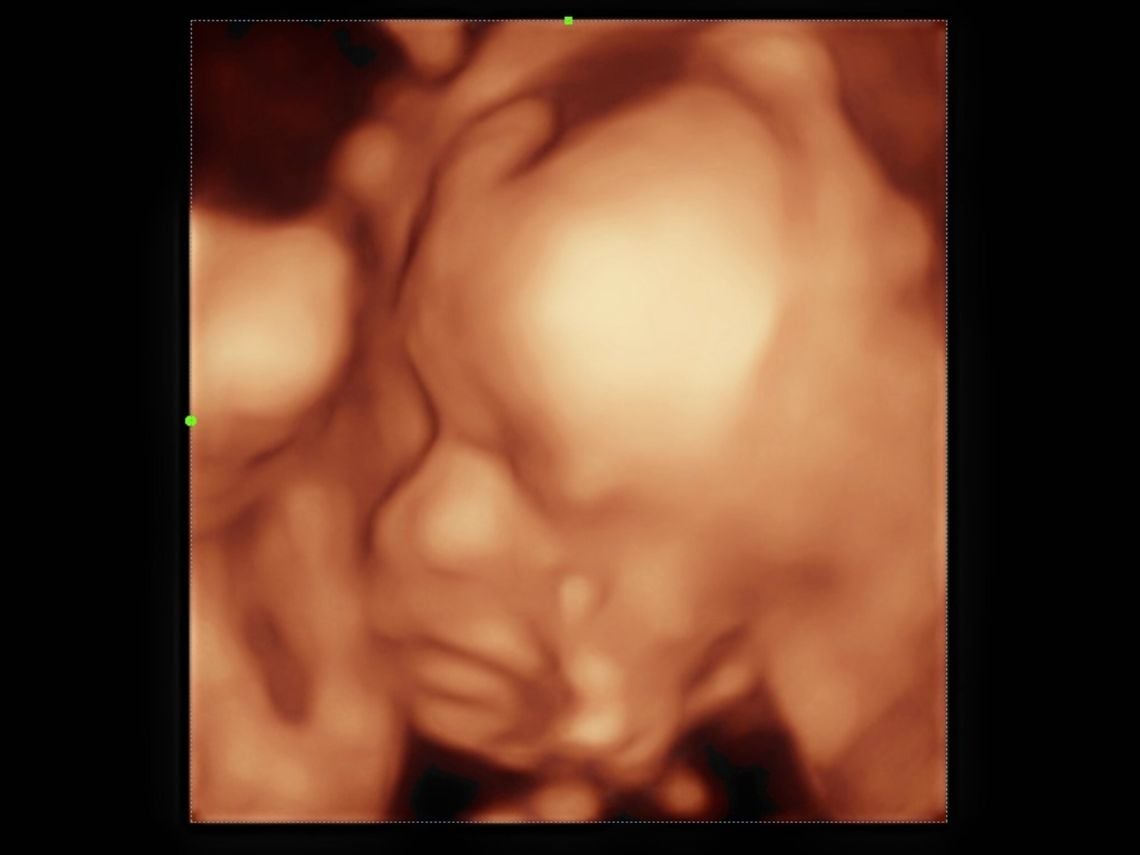

Para determinar si los bebés podían o no distinguir sabores, las autoras de la investigación se basaron en las ecografías 4D, a través de las que observaron cómo reaccionaban a diferentes sabores transferidos al líquido amniótico y su entorno fetal después de haber sido ingeridos por sus madres.

Por el contrario, con el sabor a col rizada, “los recién nacidos bajaban la comisura de la boca y levantaban el labio superior”. En este caso, encontraron “una tasa más alta de reacciones de cara de llanto”.